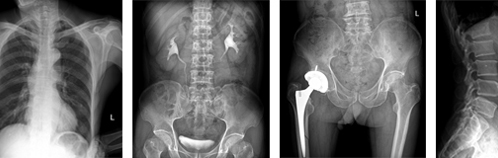

目前臨床對于16層CT的認可主要集中在三維成像領域上的突破.在16層CT的產品平臺上,常規(guī)掃描就能實現(xiàn)滿足三維成像的要求,因此16層也被稱為三維CT,三維成像給臨床診斷帶來了更精確更豐富的診斷信息,我們以臨床為例:

如上圖所示,相鄰的三張軸位圖像未見明顯異常,根據(jù)傳統(tǒng)軸位圖像很難得到準確的臨床診斷。

同一病人利用容積數(shù)據(jù)進行三維處理后,高品質MPR和三維圖像上則清晰顯示了縱向排列的腹腔干與腸系膜上動脈相鄰近,血管發(fā)生變 異,近端血管閉塞,為臨床提供了精確的診斷信息。

從上面的例子可以看到,能否為臨床提供高品質的三維影像成為了16層CT的核心價值,而東芝新一代的 全景三維16層CT擁有最為  先進的3項核心技術,在16層核心價值上的表現(xiàn)自然值得期待。